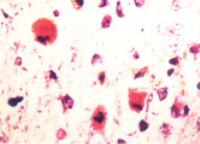

Hisopathology

- primary target of bilirubin encephalopathy is the neuron

- intracellular bilirubin only identified in very high bilirubin concentrations, and even then is difficult

- changes are acute necrosis, similar in appearance to hypoxic-ischemic injury or hypoglycemia

- dead neurons may become encrusted in calcium or iron salts

- protoplasmic and/or fibrillary astrocytes appear in a few days